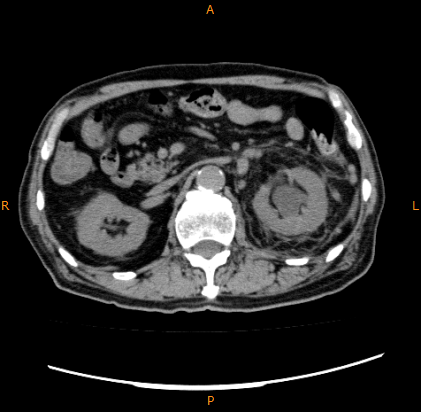

腹部単純CT、左水腎症、左腎周囲炎

左水腎症がみられ、腎周囲脂肪織に炎症が波及した所見がみられるが、膿瘍形成はみられなかった。左腎周囲炎と診断された。